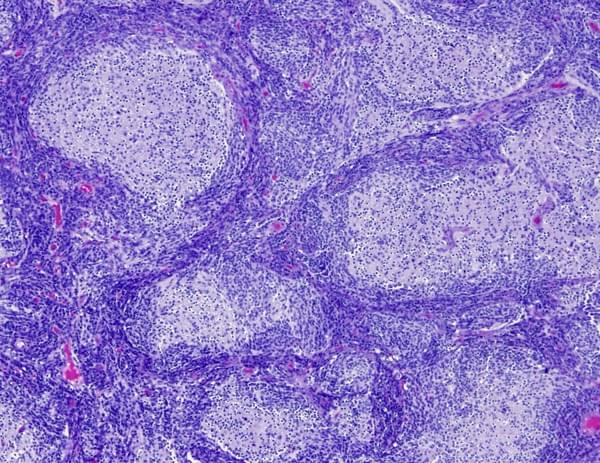

Computational pathology for cancer

Drug repositioning for Medulloblastoma

Medulloblastoma is the most common malignant (cancerous) central nervous system tumor in children. It accounts for 15 to 20 percent of all pediatric brain tumors. Medulloblastomas occur most commonly in children between ages of 3 and 8 but can be seen in children and adults of any age. Molecular studies suggest medulloblastoma is not one disease but comprises a collection of at least four distinct molecular subgroups that differ in their clinical severity and response to chemotherapy. We are using our STARGEO genomics discovery platform to refine more precise genomic subtypes of melanoma, and we are looking for personalized therapeutics to make difficult to treat subtypes more amenable to standard chemotherapeutic regimens.